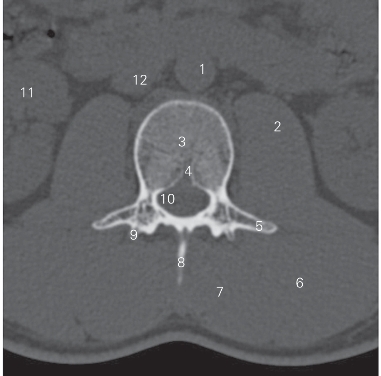

图3-1 经第2腰椎椎体的横断层CT图像(骨窗)

1 腹主动脉 abdominal aorta 2 腰大肌 psoas major

3 第2腰椎椎体 2nd lumbar vertebral body

4 椎体静脉 basivertebral veins 5 横突 transverse process

6 竖脊肌 erector spinae 7 多裂肌 multifidi

8 腰椎棘突 spinous process of lumbar vertebra

9 上关节突 superior articular process 10 侧隐窝 lateral recess

11 右肾 right kidney 12 下腔静脉Inferior vena cava